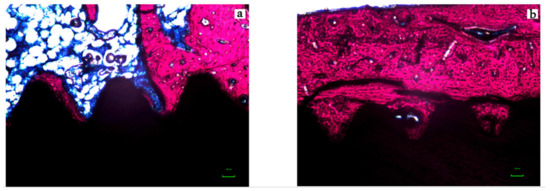

2.5. Histological Preparation and Histomorphometric Analysis

3. Results